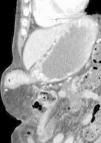

Mujer de 95 años con vómitos y dolor epigástrico de 2 días de evolución. A la exploración, tumoración epigástrica irreductible dolorosa (fig. 1 reconstrucción 3D por TC). En la tomografía computarizada se objetiva una hernia epigástrica que contiene el antro gástrico con mucosa edematosa (fig. 2 corte coronal, fig. 3 corte sagital). Se interviene de urgencias evidenciando defecto de pared de 4cm, por el cual protruye una zona circular de 2×2cm de antro gástrico, con área fibrótica circular en su superficie que no obstruye el paso. Se reintroduce el contenido herniario, que presenta un aspecto viable a la cavidad, y se coloca malla de polipropileno fijándola con puntos sueltos de material irreabsorbible, siendo alta al tercer día de ingreso sin complicaciones.